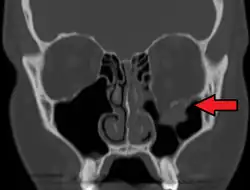

Radiography, imaging of tissues using X-rays, is used to rule out facial fractures.[2] Angiography (X-rays taken of the inside of blood vessels) can be used to locate the source of bleeding.[11] However the complex bones and tissues of the face can make it difficult to interpret plain radiographs; CT scanning is better for detecting fractures and examining soft tissues, and is often needed to determine whether surgery is necessary, but it is more expensive and difficult to obtain.[4] CT scanning is usually considered to be more definitive and better at detecting facial injuries than X-ray.[3] CT scanning is especially likely to be used in people with multiple injuries who need CT scans to assess for other injuries anyway.[12]